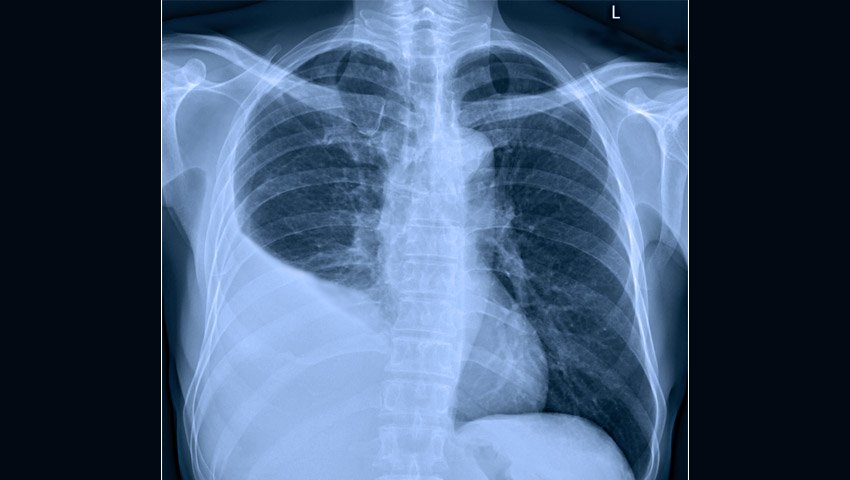

La Rx Tórax frente y en decúbito lateral pueden ayudar en el diagnóstico de derrame pleural y en la determinación de la necesidad de realizar toracocentesis y/o la ubicación del drenaje. Sin embargo, las radiografías por sí solas no pueden diferenciar el empiema del derrame paraneumónico. Los signos radiográficos de derrame pleural incluyen el borramiento del ángulo costofrénico y/o la presencia de línea de despegamiento pleural. La presencia de niveles hidroaéreos sugiere microorganismos formadores de gas, neumotórax o fístula broncopleural.

Imagen de un tórax normal por radiología (frente)

(Nótese como los ángulos terminan en cuña, eso se llama ángulos costofrénicos)

Imagen de un tórax con Supuración Pleuropulmonar derecho

(Nótese como se "borro" el ángulo costofrénico derecho por la ocupación de líquido en el espacio interpleural)